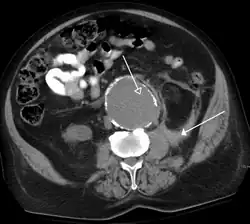

FIGURE 2. Contrast enhanced CT demonstrating parenchymal enhancement of the intra-abdominal organs in the portal venous phase (axial left, coronal reformat right).

The most common technique is to perform portal venous phase imaging in the abdomen and pelvis (approximately 60–90 seconds after contrast administration, figure 2). This results in near optimal contrast opacification of the majority of the solid abdominal organs and it is used for a wide variety of indications: nonspecific abdominal pain; hernia; infection; masses (with a few exceptions such as hypervascular, renal, and some hepatic tumors); and in most follow-up examinations. As a general rule, this single phase is adequate unless there is a specific clinical indication that has been shown to benefit from other phases.